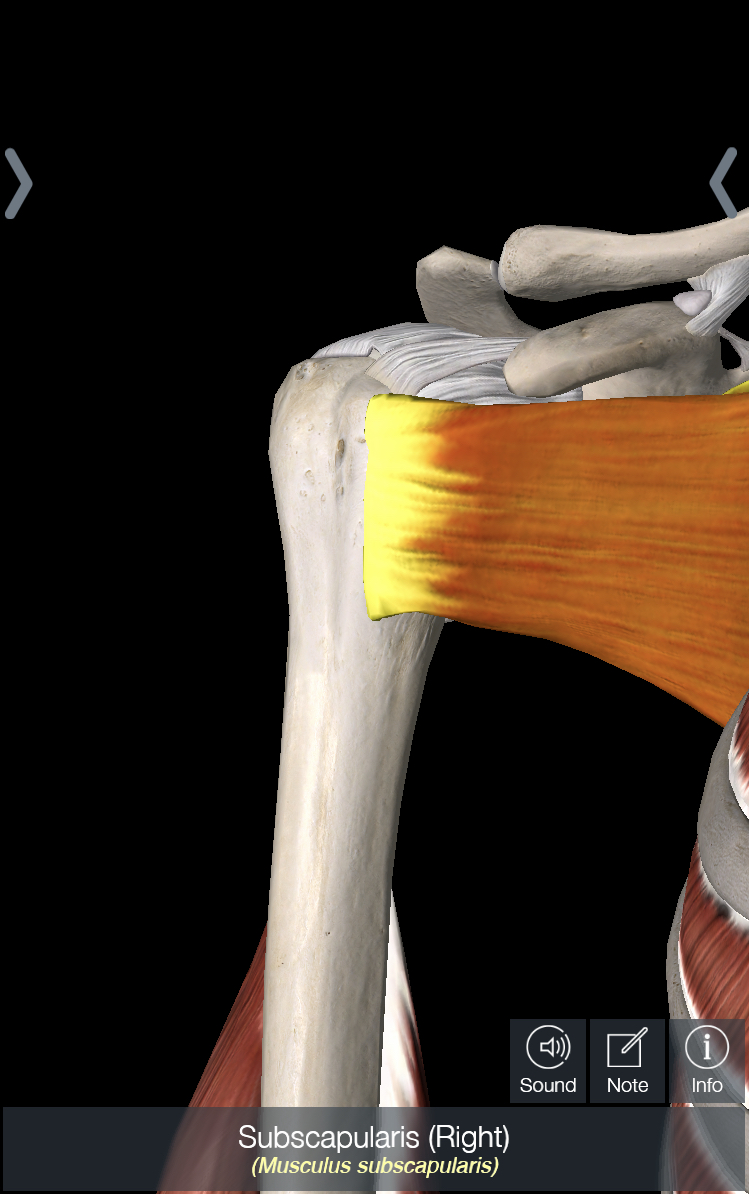

The shoulder joint – also known as the glenohumeral joint – is a ball and socket joint, with a piece of connective tissue called the labrum that surrounds the socket to make the joint more stable. The muscle that is most likely to be torn in an Americana is the subscapularis, which is one of the 4 muscles of the rotator cuff and crosses in front of the shoulder joint. In terms of ligaments, there is a capsule that surrounds the shoulder joint; this can be thought of as a large piece of tissue that surrounds the joint with several areas that are thickened throughout; these are considered ligaments. Of these ligaments – i.e. the ligaments contained within the capsule of the shoulder – the one we care about the most is the inferior glenohumeral ligament (IGHL). In addition, the coracohumeral ligament, which attaches from the front of the scapula to the ball of the shoulder joint, is also important.

In all the pictures below, we are looking at the shoulder from the front. In picture 1, I have removed everything except for the shoulder capsule. In picture 2, I have highlighted the IGHL, which is one of the most stressed ligaments in the shoulder with an Americana. You can imagine that if someone is rotating your shoulder upwards, that will cause this ligament to rotate upwards as well, making it the main part of the capsule being stressed. In picture 3, I have rotated the picture about 60 degrees and highlighted the coracohumeral ligament. And last but not least, in picture 4 I have highlighted the subscapularis.

The Americana works primarily by placing the shoulder into hyper-external rotation and secondarily by moving the ball of the shoulder forward in the socket – what we term “anterior translation.” In the first situation, putting the shoulder into such a high degree of external rotation will eventually tear the ligaments in the front of the shoulder – the IGHL and coracohumeral ligament – and the subscapularis. In the second situation, if pressure is being placed on the back of the shoulder and pushing it forward, the ball of the shoulder can pop out the front of the socket, which will damage the ligaments mentioned above and possibly tear the labrum.

If you damaged the ligaments in the front of the shoulder and/or the labrum, it is very important to strengthen the shoulder muscles, especially the rotator cuff. The rotator cuff is the primary set of muscles that provide stability to the shoulder joint, and when the ligaments are damaged, the rotator cuff is required to do more work to stabilize the joint. There are a variety of rotator cuff exercises that you can find online, but it is best to work with a physical therapist to 1) make sure you are doing the exercises correctly and 2) find exercises that are appropriately challenging.